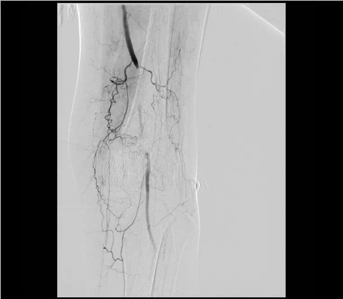

動脈閉塞處支架植入

血管內(nèi)微創(chuàng)介入治療(球囊擴張、支架植入)是國際上治療下肢動脈缺血疾病最常用、首選的一種微創(chuàng)、安全、高效的治療方法。